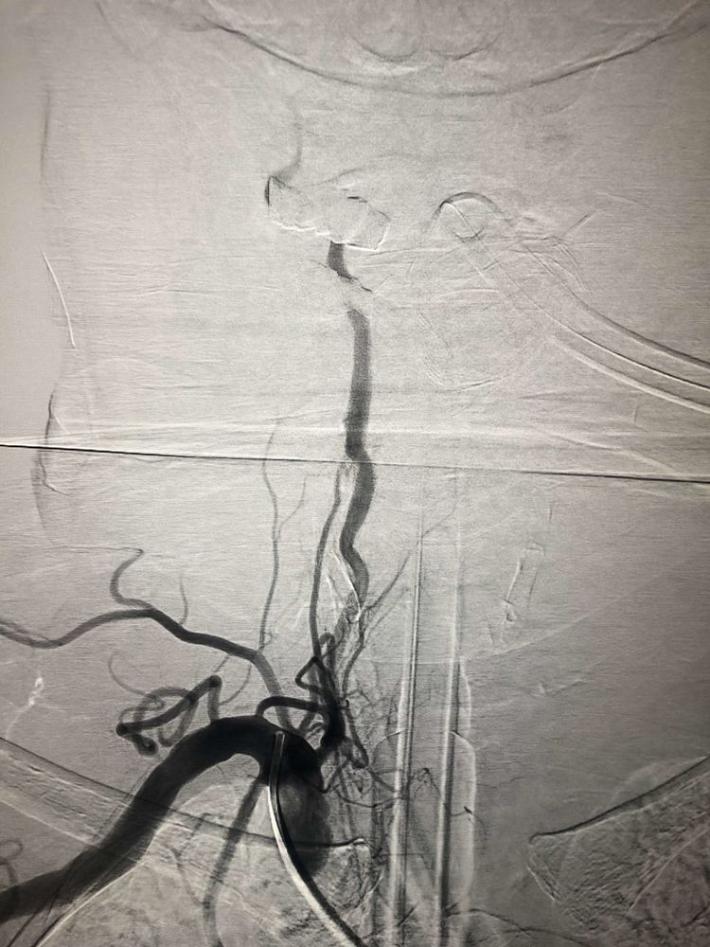

双侧颈内动脉

双侧椎动脉

左侧椎动脉

右侧椎动脉造影:基底动脉中段充盈缺损,基底动脉尖丢失。提示基底动脉中段原位狭窄基础上血栓形成,血栓脱落栓塞基底尖。

微导丝微导管通过闭塞部位,经微导管造影,确认在远端真腔。

一把拉通后,前向血流即刻恢复至3级,双侧小脑上动脉、大脑后动脉、基底动脉尖显影。

现基底动脉残余狭窄约40%,观察20min前向血流3级;斑块累及小脑前下动脉;右侧丘脑出血转化,尽可能避免双抗,综合考虑后放弃急诊支架植入,术后给予盐酸替罗非班泵入维持血流稳定。